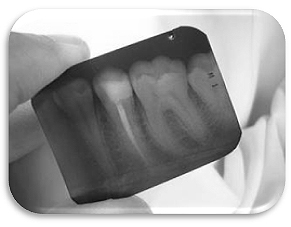

Cuando esto sucede hay que recurrir a la endodoncia o tratamientos de conductos radiculares. La endodoncia se conoce popularmente como “matar el nervio”. Una endodoncia consiste en limpiar y eliminar toda infección del interior de los conductos del diente asegurándonos que se llega hasta el final

de la raíz del diente. Para ello se utilizan dispositivos que ayudan a localizar la longitud de la raíz y además radiológicamente se va comprobando el tratamiento en las distintas fases.